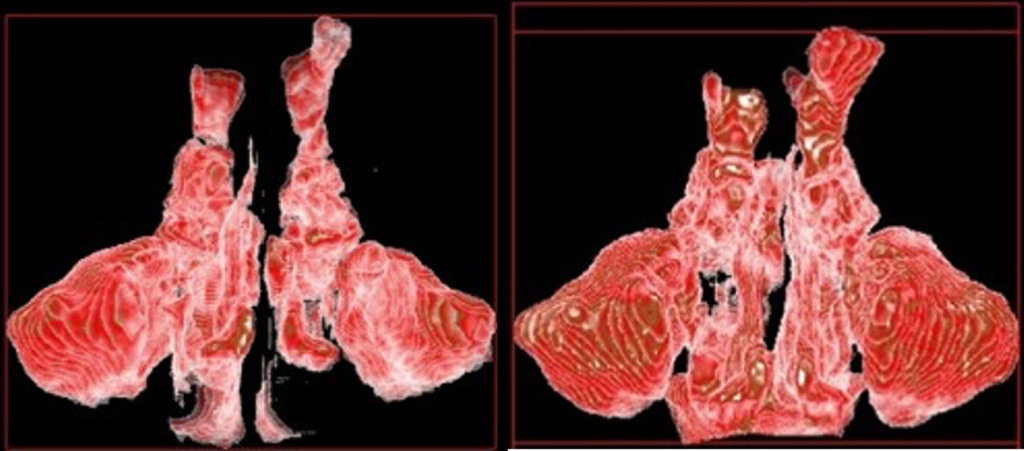

気道容積

鼻腔容積

歯列

※気道容積・鼻副鼻腔容積の変化イメージ